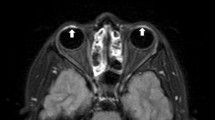

Figure 5 shows representative images (presented only for the samples treated with Gd and 17O). After Gd administration, the TE500 image showed a visual signal decrease in the anterior chamber at 4 h and a strong signal decrease in the vitreous cavity at 26 h; the TE3200 image showed a visual signal decrease in the anterior chamber at 1 h and a decrease in the vitreous peripheral signal at 8 h. After 17O administration, the signal decrease in the anterior chamber was observed on the graph for TE500 (Fig. 3a), but it was visually obscure, and there might be a slight signal decrease visually in the vitreous cavity after 12 h. The TE3200 image showed a visual signal decrease in the anterior chamber at 0.5 h, and a gradual signal decrease in the vitreous cavity from the periphery at 1 h. In both solutions with TE4500, the tendency for signal decrease was more remarkable compared to TE3200. In 3D-real IR images, only the Gd sample showed a strong signal increase. Signal increases in the anterior chamber were observed at 0.5 h, and their distribution in the vitreous cavity gradually increased at 2 h and later.

In this study, 3D-real IR for T1 changes and 3D-T2W with super-long TE for T2 changes were found to be useful for visualizing intraocular distribution. Both sequences are 3D acquisitions, which facilitate the evaluation of detailed structures, such as distribution pathways to the vitreous. However, 3D sequences require long acquisition times, and can cause motion artifacts attributable to eye movements or blinking during scanning, which will inevitably pose problems for future human studies. To address these concerns, Tomiyasu et al. employed a single-shot sequences (i.e., HASTE) in their study on humans [7]. We therefore propose a new approach based on the application of a super-long TE using the HASTE technique, which could provide high sensitivity to T2 changes imaging, comparable to that obtained using 3D-T2W with a TE of 3200 ms (Fig. 4). A further concern is the long data duration of the 3D-T2W, which may cause blurring artifacts. Sample images obtained using 3D-T2W and HASTE sequences are shown in Fig. 6. The 3D-T2W with a TE of 3200 and 4500 ms shows more pronounced blurring artifacts than images obtained using a TE of 500 ms. In contrast, the HASTE sequence provides images without blurring artifacts, even with a TE of 3000 ms. Moreover, images can be obtained within a few seconds per slice. Thus, although it is a 2D acquisition, it can provide motion-robust and high temporal resolution. With the application of UH-T2W, HASTE would be appropriate for observation of aqueous flow dynamics with high temporal resolution in the early phase, and 3D imaging would be appropriate for a detailed anatomical interpretation of intraocular distribution.

We also established that there are differences between Gd and 17O with respect to the speed and pattern with which these drugs penetrate the vitreous cavity. Compared with Gd, we found that 17O administered via eye drops was characterized be a more rapid distribution, which is consistent with the findings of a previous study on glymphatic water transport in the rat brain in vivo [16]. In addition, the penetration of Gd into the vitreous cavity may be initiated from the peripheral through the sclera, whereas in contrast, 17O appears to be distributed from the anterior chamber side into the vitreous cavity (Fig. 5). We suspect that these differences in distribution speeds and patterns are attributable to certain pharmacodynamic properties of the drugs, such as differences in molecular weight and viscosity, which is a topic warranting further investigation.